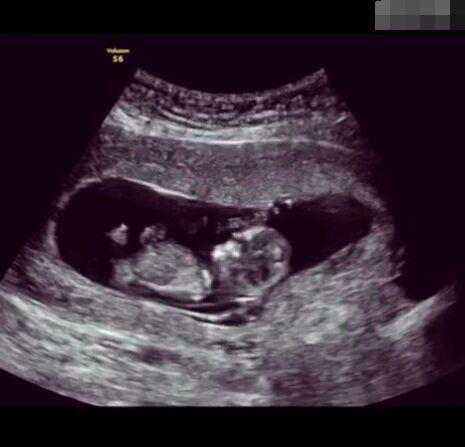

孕育生命是一件無比非凡的事!想像一下,我們都是從一個(gè)肉眼難見的小小受精卵發(fā)育而來,而這只需要一顆卵子與一顆精子的結(jié)合,就能實(shí)現(xiàn)一個(gè)生命的從無到有的過程,這是多么神奇的一件事情!

懷孕后,寶寶的性別一直是全家人的重點(diǎn)關(guān)注對(duì)象。而男女性別的差異,在基因?qū)用骟w現(xiàn)在第二十三對(duì)染色體上,如果是XY則是男孩,XX則是女孩,這都是由那枚與卵子結(jié)合的精子來決定。

那些做了B超檢查確定胎兒男女,生下來后發(fā)現(xiàn)不對(duì)的,多半是因?yàn)樵贐超檢查時(shí)寶寶太調(diào)皮,以致影響了檢查準(zhǔn)確性。就比如說,有的女寶寶在媽媽肚子里玩自己的臍帶,把臍帶夾到了兩腿中間,B超就有一定幾率拍出來好像是男寶寶的特征,導(dǎo)致被誤認(rèn)為是男孩子。還有些男寶寶過分害羞,在做B超時(shí)雙腿緊緊并攏,醫(yī)生也很難判斷男女,只好大致猜測(cè)是女孩,就又造成了誤會(huì)。因此,B超亦不是萬能的。